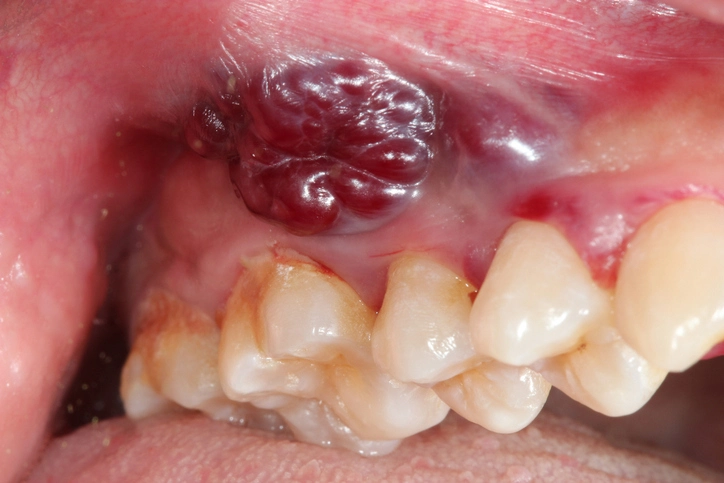

Peripheral Giant Cell Granuloma (Giant Cell Epulis)

This lesion is a reactive hyperplasia, not a true neoplasm, arising from the gingiva or alveolar mucosa.

Aetiology

- Chronic irritation

- Plaque, calculus

- Trauma from restorations or dentures

Clinical Features

- Deep red or purple gingival swelling

- May ulcerate or bleed

- Often found on the interdental papilla

Histology

- Multinucleated giant cells

- Vascular stroma

- Hemosiderin deposits

Management

- Surgical excision

- Removal of periosteum

- Curettage of underlying bone

- Elimination of local irritants